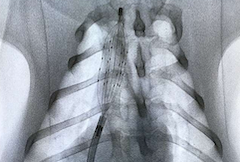

開発したバスケット型カテーテル

日本発で世界初の医療機器開発へ

国立研究開発法人日本医療研究開発機構(AMED)先端計測事業の支援を受け、平成28年下半期より、臨床応用を目的としたカテーテルデバイスの開発を開始しました。先端の単電極構造であったものを、留置性、刺激安定性および刺激部位選択性などを考慮し、多電極配置のバスケット構造にしました。現在、先端計測事業から引き続き、AMED医工連携事業の支援を受け、世界初の治験を目指し、開発を進めております。